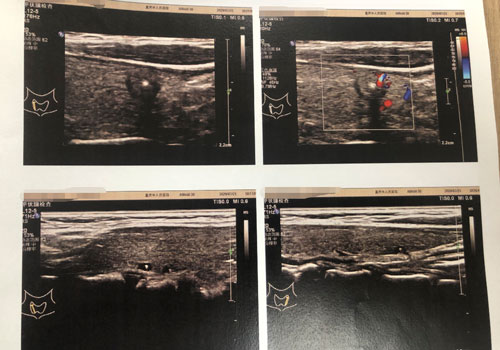

夏女士的甲状腺影像检查。院方供图